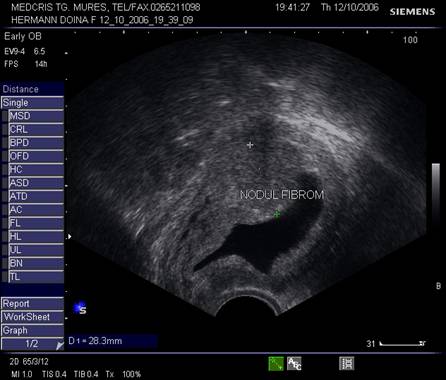

9.Sarcina si fibromul uterin

Cea mai comuna tumora uterina - leiomiomul - poate fi detectata si masurata inca de la inceputul sarcinii. Fibromul poate complica sarcina in functie de marime si pozitie. Nodulul subseros pediculat foarte rar se poate complica, in schimb nodulul submucos sau intramural creste riscul de avort spontan sau nastere prematura, dar peste 75% din aceste paciente duc sarcina la termen. Cea mai frecventa complicatie a fibromului in sarcina este necroza aseptica (25%) de obicei moderata, ea poate aparea si in lauzie. Cresterea fibromului in sarcina a fost notata in circa 22% dintre fibroame.[12]

Fibromul apare de obicei hipoecogen in uterul gravid, trebuind masurat si observat pe parcursul sarcinii.

Fig nr. 91. Nodul fibromatos submucos si sarcina